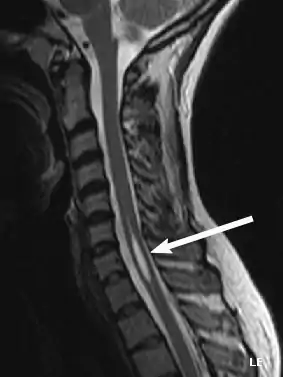

Physicians now use magnetic resonance imaging (MRI) to diagnose syringomyelia. The MRI radiographer takes images of body anatomy, such as the brain and spinal cord, in vivid detail. This test will show the syrinx in the spine or any other conditions, such as the presence of a tumor. MRI is safe, painless, and informative and has greatly improved the diagnosis of syringomyelia.[12][13][14][15][16][17][18][19][20][21][22][23]

The possible causes are trauma, tumors, and congenital defects. It is most usually observed in the part of the spinal cord corresponding to the neck area. Symptoms are due to spinal cord damage and include pain, decreased sensation of touch, weakness, and loss of muscle tissue. The diagnosis is confirmed with a spinal CT, myelogram or MRI of the spinal cord. The cavity may be reduced by surgical decompression.